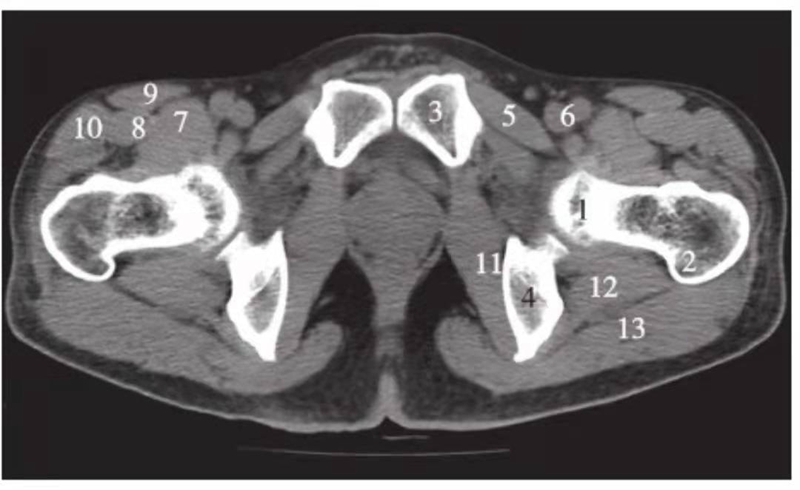

图3 股骨头凹层面(骨窗)

1.股骨头;2.星芒状结构;3.耻骨;4.坐骨;5.股骨头凹;6.髋臼窝;7.髋臼前唇;8.髋臼后唇

图4 股骨头凹下方层面(骨窗)

1.股骨头;2.髋臼前唇;3.髋臼后唇;4.前柱;5.后柱;6.髋臼前壁;7.髋臼后壁;8.髋臼窝;9.大转子;10.股骨头骨骺线;11.尾骨